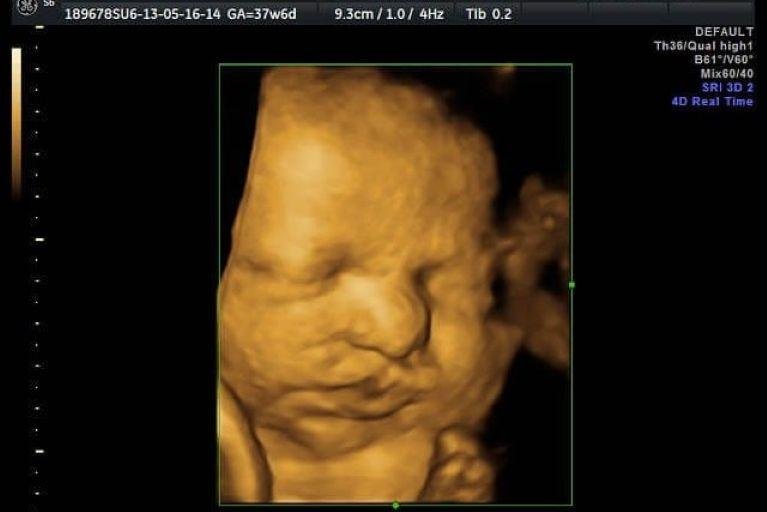

• Ultrassom Obstétrico

Acompanhamento completo da gestação com exames de alto e baixo risco, incluindo ultrassom obstétrico simples, com Doppler, Doppler com perfil biofísico fetal (PBF) e ultrassom morfológico do 1º, 2º e 3º trimestre.